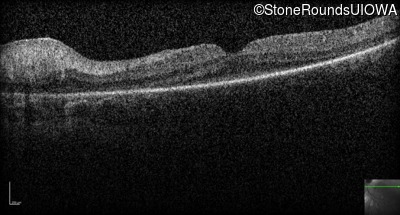

Optical Coherence Tomography - Right -

No Light Perception

Exemplar

Expanded OCT Stack

×